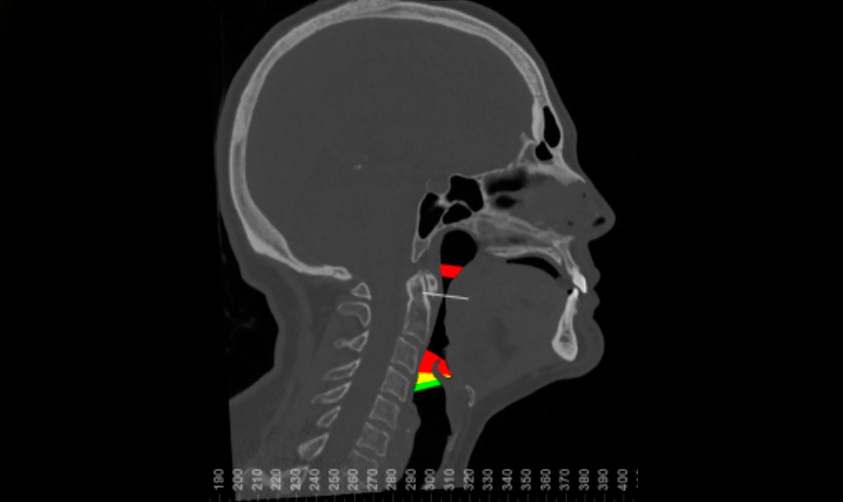

Este síndrome es una patología respiratoria causada por la apnea y/o obstrucción durante el sueño de la vía aérea.

El SAOS afecta a entre un 6% y un 8% de la población, y representa un grave impacto en la salud.

Si sientes una gran tendencia al sueño durante el día, mucho cansancio y tu sueño no es reparador, consúltanos.

Mejoramos la funcionalidad, estética y armonía facial realizando movimientos de los huesos maxilares. Mediante un estudio protocolizado digital en 3 dimensiones, aportamos la mejor tecnología para que la cirugía ortognática sea un procedimiento predecible y seguro.